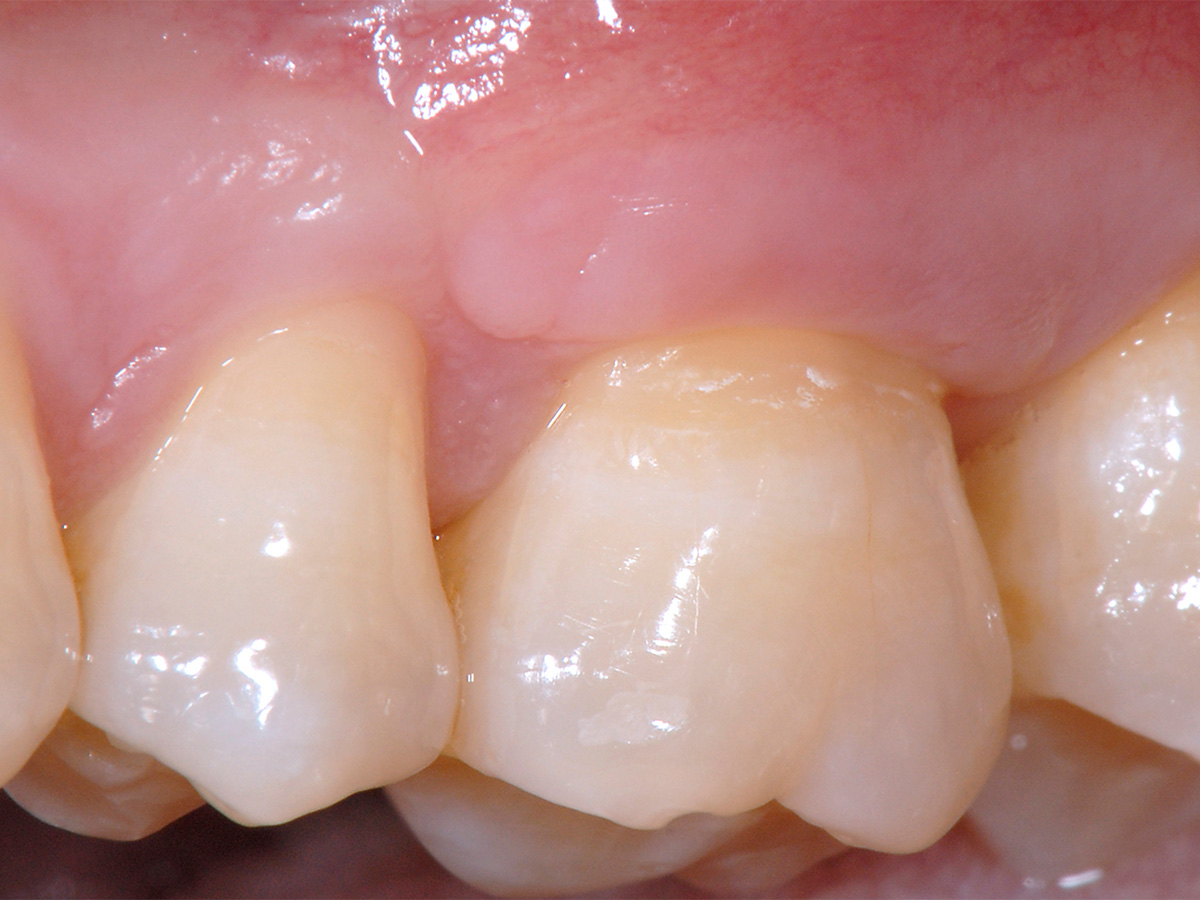

Abbildung 12

Klinische Situation des Zahnes 26 zum Zeitpunkt der Nachsorge nach drei Monaten.